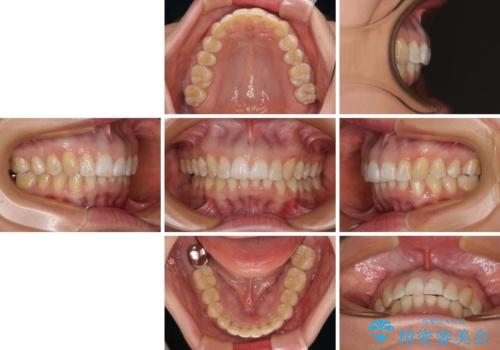

カリエールディスタライザーや部分的なワイヤー矯正を併用したことで、確実かつ短期間で治療を終えることができました。